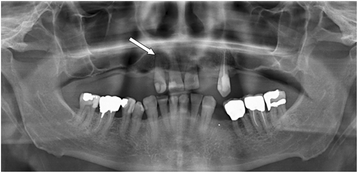

Case presentation: Patient with a history of left hip arthroplasty presented with acute onset of fever, pain and limited range of motion of the left hip. Arthrocentesis of the affected joint yielded purulent fluid and exchange of mobile parts of the prosthesis, but retention of fixed components was performed. Granulicatella para-adiacens grew from preoperative and intraoperative cultures, including sonication fluid of the removed implant. The transesophageal echocardiography showed a vegetation on the mitral valve; the orthopantogram demonstrated a periapical dental abscess. The patient was treated with intravenous penicillin G and gentamicin for 4 weeks, followed by levofloxacin and rifampin for additional 2 months. At discharge and at follow-up 1, 2 and 5 years later, the patient was noted to have a functional, pain-free, and radiologically stable hip prosthesis and the serum C-reactive protein was normal.

Conclusions: Although considered a difficult-to-treat organism, we report a successful treatment of the Granulicatella hip prosthesis infection with prosthesis retention and a prolonged antibiofilm therapy including rifampin. The periapical dental abscess is considered the primary focus of hematogenously infected hip prosthesis, underlining the importance treatment of periodontitis prior to arthroplasty and of proper oral hygiene for prevention of hematogenous infection after arthroplasty.